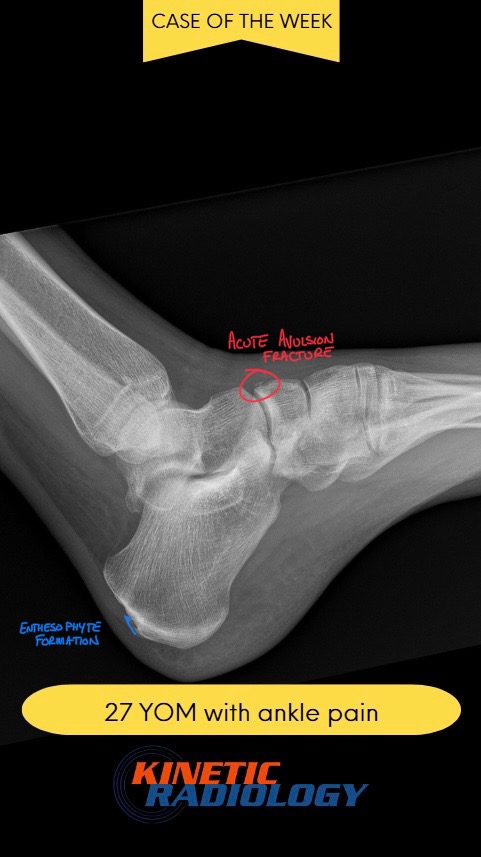

DACBR vs Chiropractor: Subtle lateral malleolar fracture

DACBR Report vs Chiropractic Report: Subtle Lateral Malleolar Fracture

DACBR vs Chiropractor: Subtle lateral malleolar fracture Fig. 1 Posterior view of the foot Fig. 2 Lateral view of the foot